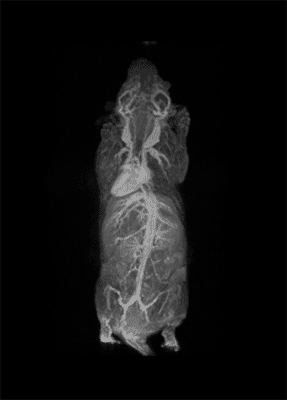

I think that also the low-field, let’s say the low/intermediate field to work at the 1 Tesla for instance as in the case of this beautiful Icon system, this gave us unique possibilities. Anytime we use a gadolinium-based agent or more in general a paramagnetic basic agent the best field is the 1 Tesla.

So, we can show that there is a real advantage of working at 1 Tesla in comparison to for instance 7 or 9 Tesla when one is using a relaxation enhancer to target a specific epitope in the region of interest.